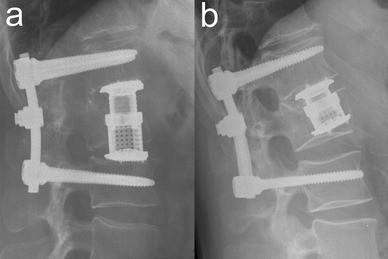

VBRD subsidence was observed in five patients (Table 4). In three of these patients, the VBRD subsided through the inferior endplate of the fractured vertebra and into the adjacent intervertebral disc (Figs. 2, 3). In the other two patients, the VBRD subsided into the cancellous bone until the inferior endplate was reached (Fig. 4). VBDR subsidence through the inferior endplate was already apparent intraoperatively (one case) or on first radiograph after postoperative mobilization (two cases), whereas VBDR subsidence into the cancellous bone occurred later but became evident on follow-up radiographs within 3 months post surgery. When comparing patients with and without VBRD subsidence after monosegmental ACR, however, differences in monosegmental (4.0 ± 2.6° vs. 2.2 ± 2.7°, P = 0.22) and bisegmental (5.8 ± 3.0° vs. 4.9 ± 4.0°, P = 0.67) loss of correction did not reach significance.

First illustrative case of VBDR subsidence through the inferior endplate after monosegmental ACR. Axial (a), sagittal (b) and coronal (c) CT reconstructions showing a complete burst fracture of L1. The axial CT reconstruction at the level of the inferior endplate of the fractured vertebra (a) reveals multiple fracture lines at the inferior end plate. Intraoperative lateral radiograph (d) showing monosegmental VBRD placement. Postoperative lateral radiographs at 3 days (e), 1 month (f), 4 months (g) and 34 months (h after implant removal) demonstrating VBDR subsidence through the severely compromised inferior endplate and into the adjacent intervertebral disc